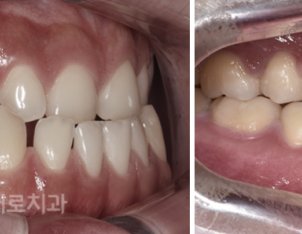

교정 전/후

하지만 이러한 양악전 교정은

수술 전 6개월~1년 정도의

교정 치료 기간이 필요하며,

수술 후 마무리 교정에도 6개월~1년 정도의

기간이 소요되기 때문에 교정 기간이

상대적으로 길다는 단점이 있었어요.

또한 수술 전 준비 교정 기간 동안

일시적으로 부정교합이 더 심해지는

증상이 발생할 수도 있다고 했어요.